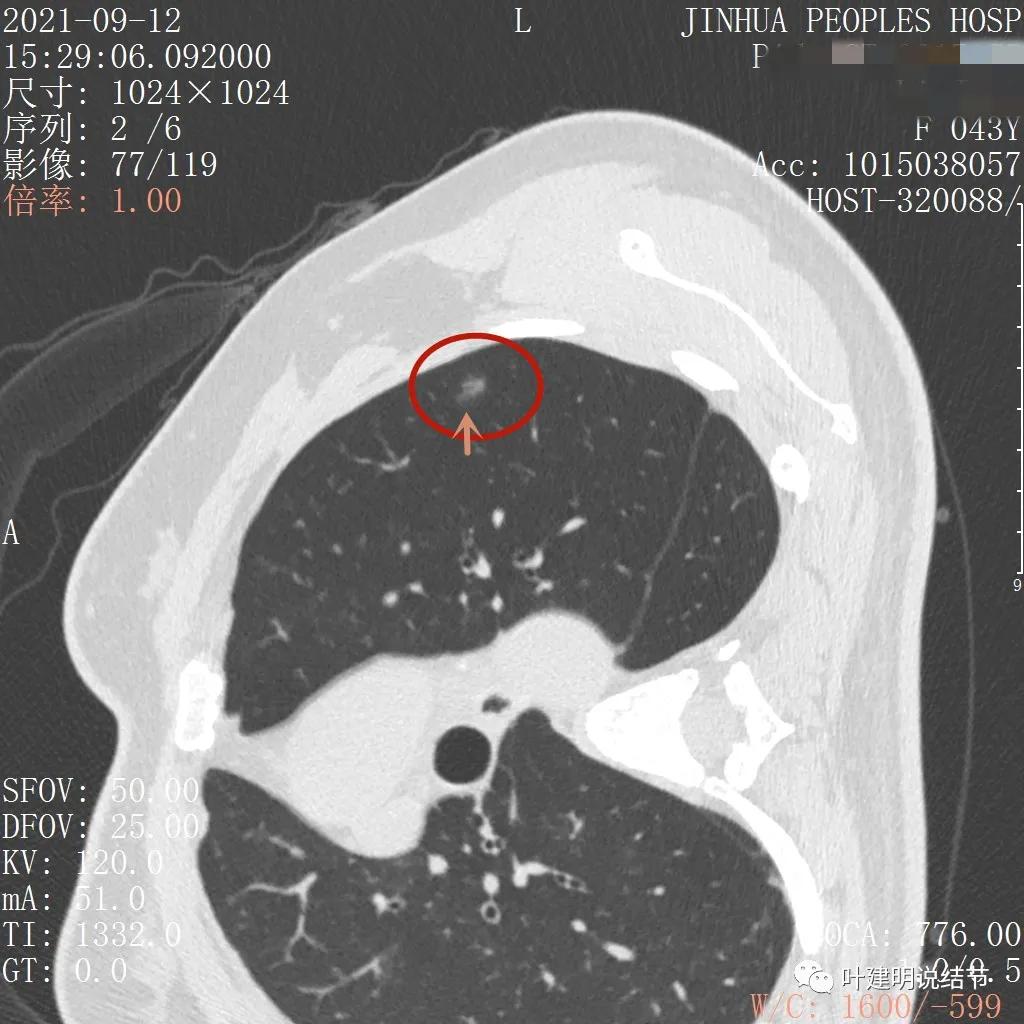

上图层面也显示病灶边缘欠清,有些模糊,虽总体轮廓还是比较清晰

从以上靶扫描图像上看,给人的印象是肿瘤范畴的结节,是混合磨玻璃结节,但磨玻璃部分的密度偏低,有的边缘显模糊,中间有点状高密度,也有微小血管进入,应该至少微浸润性腺癌可能性大。持续存在已经2月余,位置又还靠边上的,可考虑手术切除。下面再来瞧瞧后处理重建的图像: